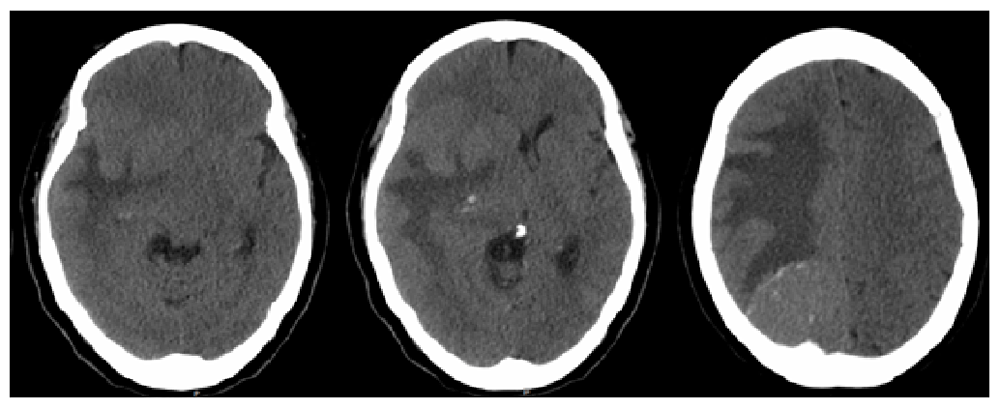

A 64-year-old Hispanic female with a past medical history of type 2 diabetes mellitus and hypertension presented with a chief complaint of left hemiparesis and paresthesias and was activated as a code stroke. History was limited due to the patient being Spanish-speaking only. She did not receive tPA because she stated her left-sided symptoms were not new and she had progressively worsening clumsiness of her left side and that she had been falling to her left. She presented to urgent care two weeks prior to presentation after sustaining a mechanical fall at home. She was diagnosed with a left bimalleolar fracture, placed in a cast, and scheduled for outpatient follow up with orthopedics for surgical evaluation. Computed tomography (CT) of head revealed a right occipital mass with significant vasogenic edema causing 12mm of midline shift (Figure 1).